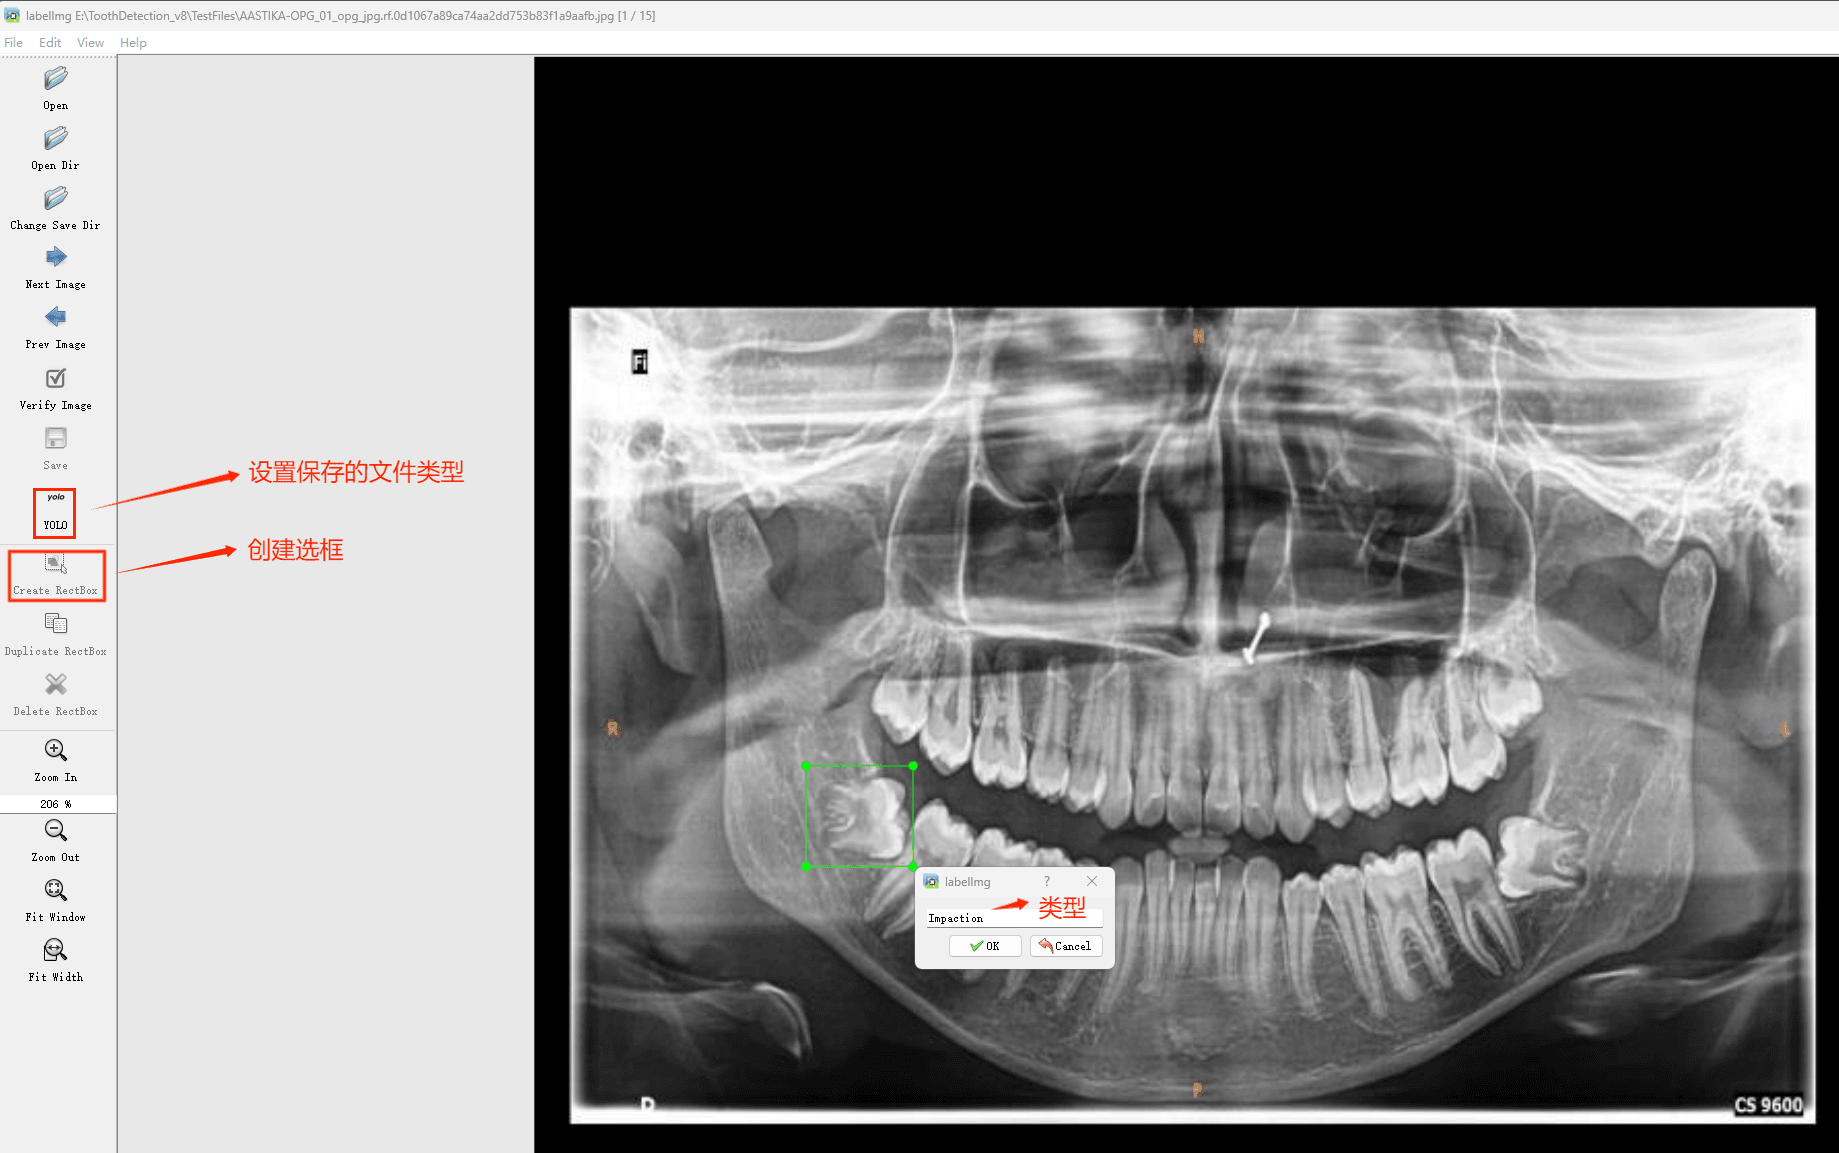

通过搜集关于数据集为各种各样的口腔牙齿CT影像相关图像,并使用Labelimg标注工具对每张图片进行标注,分6检测类别,分别是’阻生牙’,’龋齿’,’根管治疗’,’修复体’,’牙体修复’,’残根’。

目标检测标注工具

(1)labelimg:开源的图像标注工具,标签可用于分类和目标检测,它是用python写的,并使用Qt作为其图形界面,简单好用(虽然是英文版的)。其注释以 PASCAL VOC格式保存为XML文件,这是ImageNet使用的格式。此外,它还支持 COCO数据集格式。

初识labelimg

打开后,我们自己设置一下

在View中勾选Auto Save mode

接下来我们打开需要标注的图片文件夹

并设置标注文件保存的目录(上图中的Change Save Dir)

接下来就开始标注,画框,标记目标的label,然后d切换到下一张继续标注,不断重复重复。